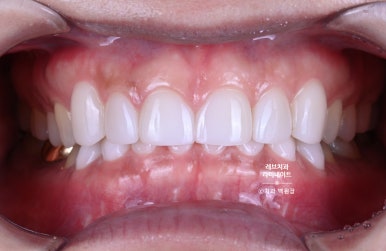

윗니와 아랫니의 색상차이를 확연히 구별하실 수 있겠죠?

위 치아는 라미네이트 치료가 되어 있으시지만, 아래 치아는 자연치 그대로입니다.

이렇게 보시면, 확실히 윗 치아와 아래 치아의 차이를 느끼실 수 있을거에요.

그래서 이렇게 마무리 된 상황!!!

약간의 잇몸성형을 통해 아랫니가 조금 더 보이게 함으로써 자연스러움을 추가하였습니다.

그리고 위 치아와 아래 치아 색상의 조화를 이루어 깔끔한 이미지를 가지실 수 있게 도와드렸습니다.

길이를 단정하게 맞추고, 색상을 개선하니 정말 20년은 젊어보이는 느낌이 들더라구요.